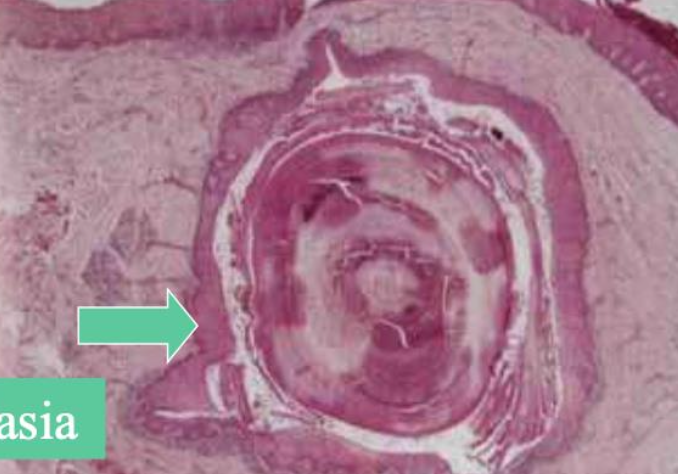

Necrotizing sialometaplasia (壞死性涎腺變生) 缺血 → 局部破壞性發炎: 局部麻醉劑(Dental injection) 、不合的假牙 軟硬顎連接處、小唾液腺 46y

• 火山口狀潰瘍,不太痛 (與潰瘍大小不成比例)

• 5-6 週自己會好,持續 2 週懷疑惡性

• Duct 鱗狀化生 (Squamous metaplasia, ~SCC)

• 腺泡壞死(acinar necrosis)

• 小葉結構完整

• 無細胞異生 (no cytologic atypia)